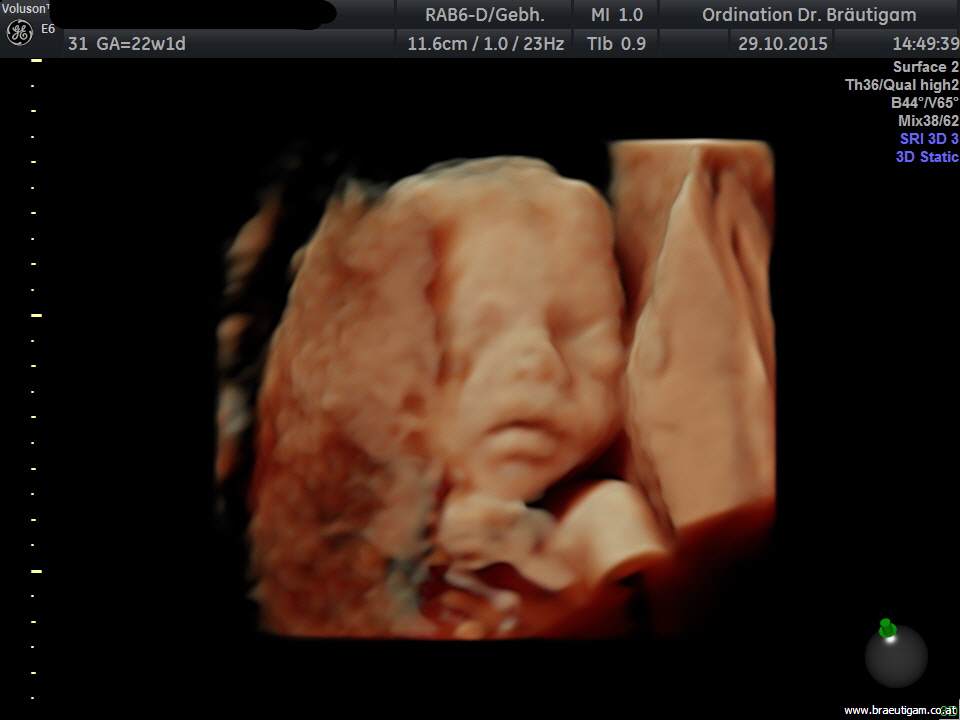

d.h. pränataler Ultraschall (Messung der Nackendicke, Organscreening) einerseits, andererseits kann noch eine Untersuchung mittels 4D-Ultraschall durchgeführt werden,

wo ein dreidimensionales Bild von Ihrem Kind angefertigt werden kann.

Dieses ermöglicht die Diagnostik einiger Fehlbildungen wie etwa der Lippen-Kiefer-Gaumenspalte, andererseits kann so das erste "Foto" von Ihrem noch ungeborenen Kind gemacht werden, was die Mutter-Kind-Beziehung zusätzlich fördert.